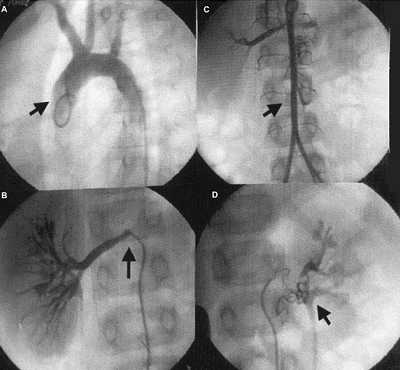

Метод внутривенной урографии

Внутривенная урография – это рентгенологическая диагностика мочевыделительной системы, которая включает почки, уретру и мочевой пузырь. При обычном рентгене мочевыводящие пути исследовать затруднительно. Внутривенная урография позволяет реально оценить состояние почек и мочеточников, а также диагностировать различные патологии мочевыделительной системы. В вену вводится специальное контрастное вещество, которое при попадании в кровоток скапливается в почках, а затем выводится естественным путем.